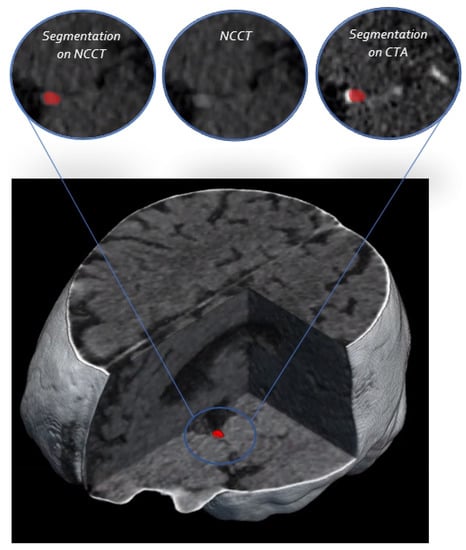

Fully Automated Thrombus Segmentation on CT Images of Patients with Acute Ischemic Stroke